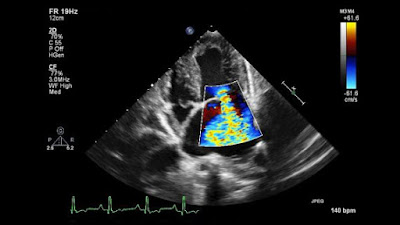

Today's appointment was my long awaited, 23 weeks, appointment to see the cardiologist to begin the process of finding out why I've had so many disconcerting heart symptoms. Nothing terribly dramatic but concerning when you don't why they are happening. Today's visit took the whole afternoon with first an ECG, next blood pressure and then I got to see the cardiologist. After much questioning I was then sent to have an echo cardiogram which was very interesting. Unlike many other tests you get to watch the screen as the technician takes readings from various angles. It was fascinating to watch the different valves which looked like kicking legs and then on different settings see and hear the blood flow. Then I was supposed to be fitted with a 7 day heart monitor but they didn't have any available, good old NHS, so I'll have to wait for a letter telling me to come in for one. That should throw some light on the problem as from today's tests my heart and valves all appear normal.